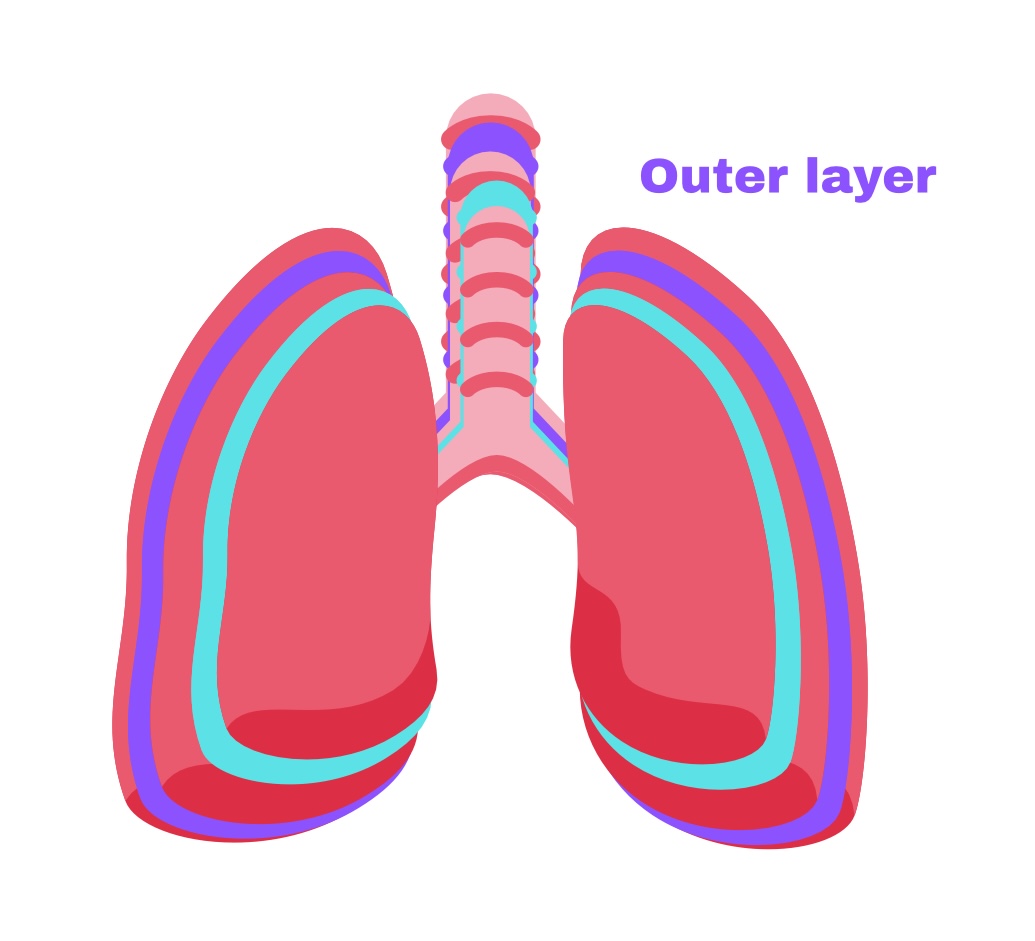

The Lungs=

Pleura

Pleura

membrane around lungs

Partial pleura

Outer layer

Visceral pleura

Deep layer (surface of organ)